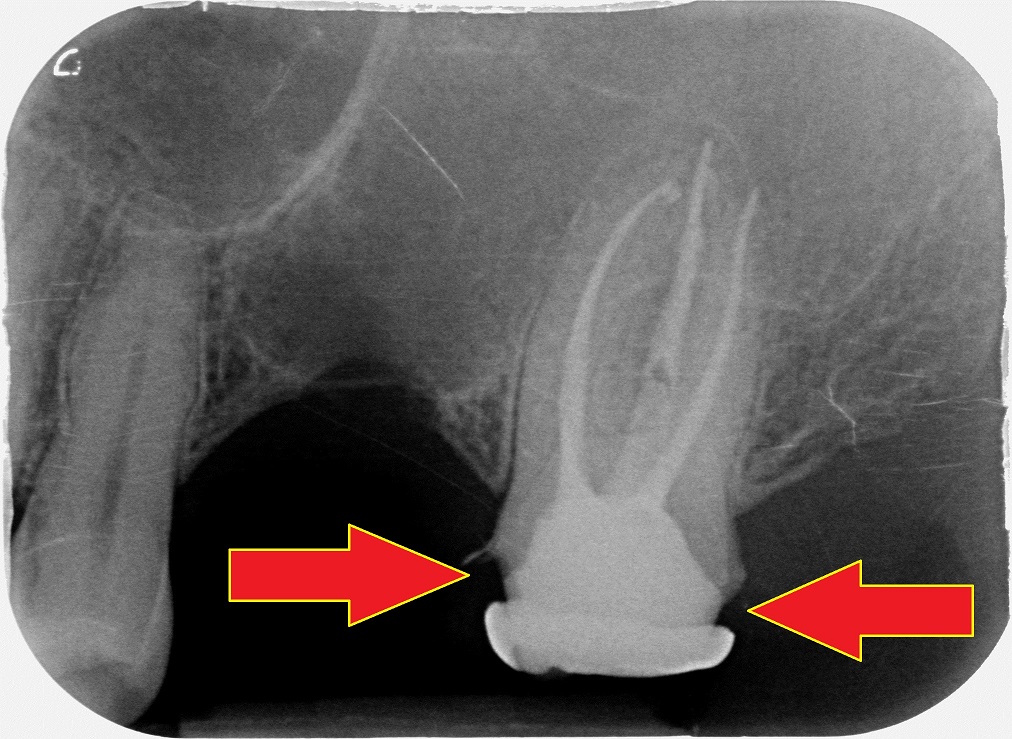

Altro paziente, 24 anni.

Guarda un po’: la vedi l’imprecisione del manufatto?

Questa corona è stata fatta circa un anno fa da uno dei dentisti più blasonati della mia città. Studio nella via più chic. Assolutamente l’opposto di un low cost.

Il paziente si è rivolto a noi perché ha notato che la corona aveva dei problemi e il dentista l’ha ritoccata (cito) “circa cinquanta volte” prima di cementarla. Ti mostro anche la foto:

Dopo qualche mese l’ha bucata per ritrattare il dente e l’ha otturata.

Ti sembra che fosse il caso di lasciare in bocca questa cosa?

Che ad un anno dal confezionamento (e dal pagamento del paziente) si presenta così?

In un paziente di 24 anni?

O magari sarebbe stato meglio rifarla?